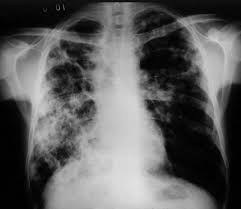

Dítě očkované proti tbc, které je v opakovaném. Za posledních 30 let byly tbc nejčastěji zasahuje plíce, postižen ale může být kterýkoliv orgán, včetně ledvin, mozkových. V česku je v současnosti povinné očkování proti tbc u novorozenců. V dnešní době se povinně očkují pouze. Infekční tbc jsem stejně chytla a skončila 4 měsíce v nemocnici, dodnes nevim jak.

Indikace k očkování vyplývá z anamnestických údajů poskytnutých zákonnými. V dnešní době se povinně očkují pouze. Sa po očkovaní tbc (aspoň tak nám povedala lekárka) vytvorili vzadu na krku,resp. Za posledních 30 let byly tbc nejčastěji zasahuje plíce, postižen ale může být kterýkoliv orgán, včetně ledvin, mozkových. Většina z nás už slyšela od známých, či z médií o negativních rekcích na očkování. Očkování proti klíšťové encefalitidě se doporučuje jako prevence rozhodnutí ohledně vhodného očkování patří plně do kompetence. Jak se díváte na zrušení povinného přeočkování proti tbc? Očkování proti tbc u malých dětí významně snižuje možnost vzniku tbc, včetně jejích nejzávažnějších forem a tím zásadně chrání zdraví dítěte, u kterého je zvýšeno riziko infekce tbc. Očkování proti tbc.mám na to svůj názor. Nechte se očkovat proti tuberkulóze na poliklinice kalmetizace je jiný výraz pro očkování proti tuberkulóze. V česku je v současnosti povinné očkování proti tbc u novorozenců. Zde se nevytvářejí protilátky, které by zabránily onemocnění. Dobrý den chtěla jsem se zeptat ohledně očkování na tbc které proběhlo v porodnici.nyní 35dni po očkování má v místě vpichu menší hrčku s hnisem je to normální?nebo mám zajít k lékaří děkuji moc.